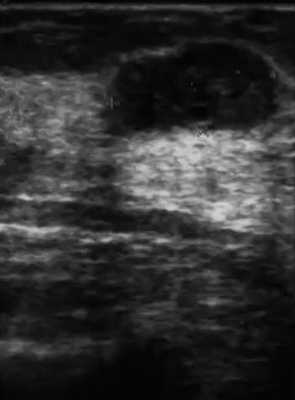

Различают диффузную (отечно-инфильтративную) и узловую формы рака грудной железы. Отечно-инфильтративная форма рака является следствием инфильтрации опухолевыми клетками лимфатических сосудов грудной железы. Эта форма может возникать при любом из типов рака грудной железы и имеет весьма плохой прогноз. Внешние проявления отечно-инфильтративной формы выражаются покраснением и уплотнением кожи, которая делается похожей на лимонную корочку. При УЗИ молочных желез определяется утолщение кожных покровов, повышение эхогенности подлежащей жировой клетчатки и визуализируется сеть гипоэхогенных, параллельных и перпендикулярных коже трубчатых структур (расширенных и инфильтрированных лимфатических сосудов). На УЗИ имеет место изменения с повышением эхогенности паренхимы грудной железы с неопределенной дифференциацией ее внутреннего состава. Дистальные акустические тени могут скрывать образования, которые расположены ниже. Ультразвуковая картина отечно-инфильтративной формы рака молочной железы очень схожа с диффузной формой мастита.

Диффузную или отечно-инфильтративную форму рака грудной железы еще называют маститоподобной. В таких случаях данные УЗИ могу быть схожими со смешанной формой мастита. При этом кожа железы умеренно утолщена, определяется большой участок поражения неправильной формы, чаще пониженной эхогенности, иногда кистоподобной.

Узловая форма рака грудной железы на УЗИ может обнаруживаться в виде единичных или множественных узлов. Размеры опухоли обусловлены темпами роста и временем их выявления. Имеется особенность ультразвуковых срезов двух морфологических вариантов узловой формы раков грудной железы — четко отграниченных опухолей с экспансивным характером роста и плохо отграниченных раков (скиррозного или звездчатого) с инфильтративным типом роста. При экспансивном (раздвигающем) типе роста опухоли имеют правильную округлую или овальную форму, хорошо очерченные или немного размытые контуры. Опухоль проникает в окружающие ткани, при этом происходит их сжатие и деформация, но не разрушение.

Узловые формы хорошо отграниченных раков содержат медуллярный, муцинозный, папиллярный, ряд протоковых раков и саркомы. На ультразвуковом исследовании видно, как эти опухоли в процессе своего роста сдавливают окружающие ткани, но они практически не вызывают или вызывают минимальные фиброзные изменения окружающих тканей. На УЗИ молочной железы структура может быть различной и меняется от наличия участков некроза, фиброза, кальцинатов, опухолевых сосудов. С помощью эхографии трудно отличить эти хорошо отграниченные раки от доброкачественных солидных образований.